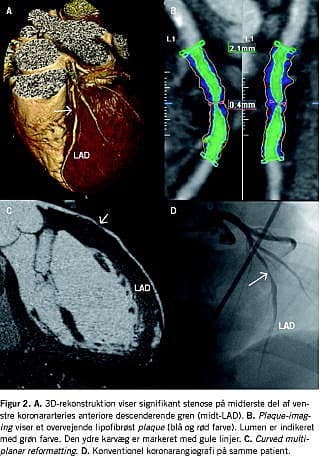

Billedanalysen foregår på en arbejdsstation med dedikeret software og vil typisk omfatte aksiale billedsnit i kombination med skrå og kurvede multiplanare rekonstruktioner gennem koronararterierne. Tredimensionelle rekonstruktioner er velegnede til at få overblik over koronaranatomien (Figur 1). Funktioner som automatisk vessel tracking, kantdetektion og kvantitativ stenosegradering er blevet almindelige i de fleste softwarepakker og har gjort evalueringen af koronararterierne hurtigere (Figur 2).

Ud over visualisering af det kontrastfyldte lumen giver CT-KAG også oplysninger om karvæggen og plaque -morfologien. Ikkestenoserende plaques og remodellering af karvæggen kan identificeres, ligesom eventuelle plaques kan karakteriseres som værende overvejende lipidholdige, fibrøse eller kacificerede (Figur 2). De kliniske implikationer af en sådan opdeling er dog fortsat uafklarede.